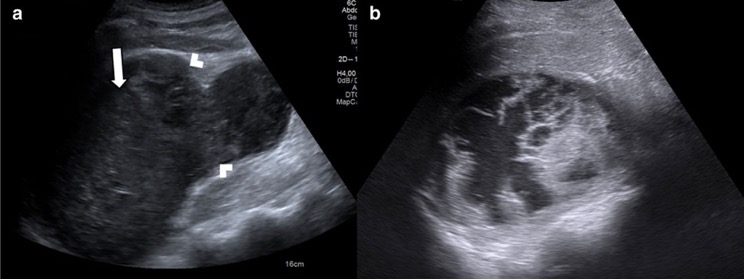

2. Pseudotumeurs rénales infectieuses et granulomateuses

- Néphrite bactérienne focale

- abcès rénal

- Tuberculose rénale

- Pyélonéphrite xanthogranulomateuse

- Sarcoïdose rénale

- Kyste hydatique rénal